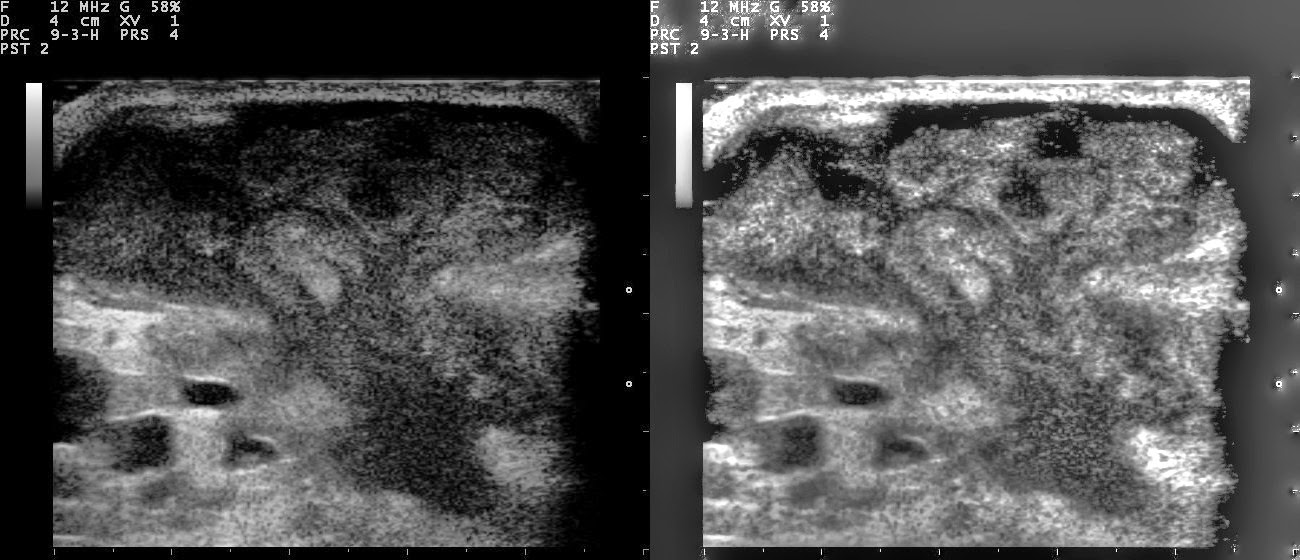

El ultrasonido mamario es un procedimiento médico no invasivo utilizado para evaluar el tejido mamario en busca de anomalías, como quistes, masas o cambios en la densidad. Durante este examen, se emplea tecnología de ultrasonido para obtener imágenes detalladas de los senos, lo que proporciona información crucial para el diagnóstico y la evaluación de la salud mamaria.

El transductor, un dispositivo manual similar a un micrófono, se mueve suavemente sobre el tejido mamario, emitiendo ondas sonoras de alta frecuencia. Estas ondas sonoras penetran en el tejido y rebotan de vuelta al transductor, donde se convierten en imágenes en tiempo real en una pantalla.